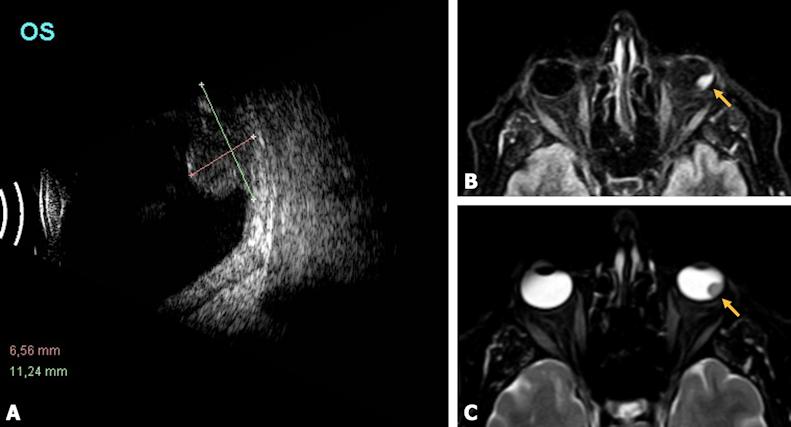

The recorded best-corrected visual acuity was 0.16 in the RE and light perception in the LE. An applanation tonometry revealed an intraocular pressure (IOP) of 38 mmHg in the LE. Anterior slit-lamp examination showed iris rubeosis, posterior synechiae and cataract. Fundus eye examination exhibited vitreous haze and hemorrhage in reabsorption with suspected inferior mass. In the RE IOP was within a normal range and the anterior segment and fundus examinations were unremarkable. B-scan ultraso-nography demonstrated an infero-temporal retinal mass, mushroom-shaped, measuring 11.24x8.2x6.56 mm (Figure 1A [Fig. 1]). Magnetic resonance imaging (MRI) was performed. It showed a well-circumscribed mass with hyperintensity in sequence T1 and hypointensity in sequence T2, consistent with choroidal melanoma (Figure 1B and C [Fig. 1]). Systemic extension test was negative for metastasis. Enucleation was performed on the basis of intraocular tumor consistent with choroidal melanoma with secondary vitreous hemorrhage and inflammatory signs.

Figure 1: A: B-scan ultrasonography showing a mushroom-shaped mass protruding through the retina into the vitreous cavity, measuring 11.24 mm in the largest basal diameter and 6.56 mm in height. B: Sequence T1 and C: sequence T2 magnetic resonance imaging (MRI) showing a hyperintense and hypointense intraocular mass (yellow arrowhead), respectively, consistent with choroidal melanoma.